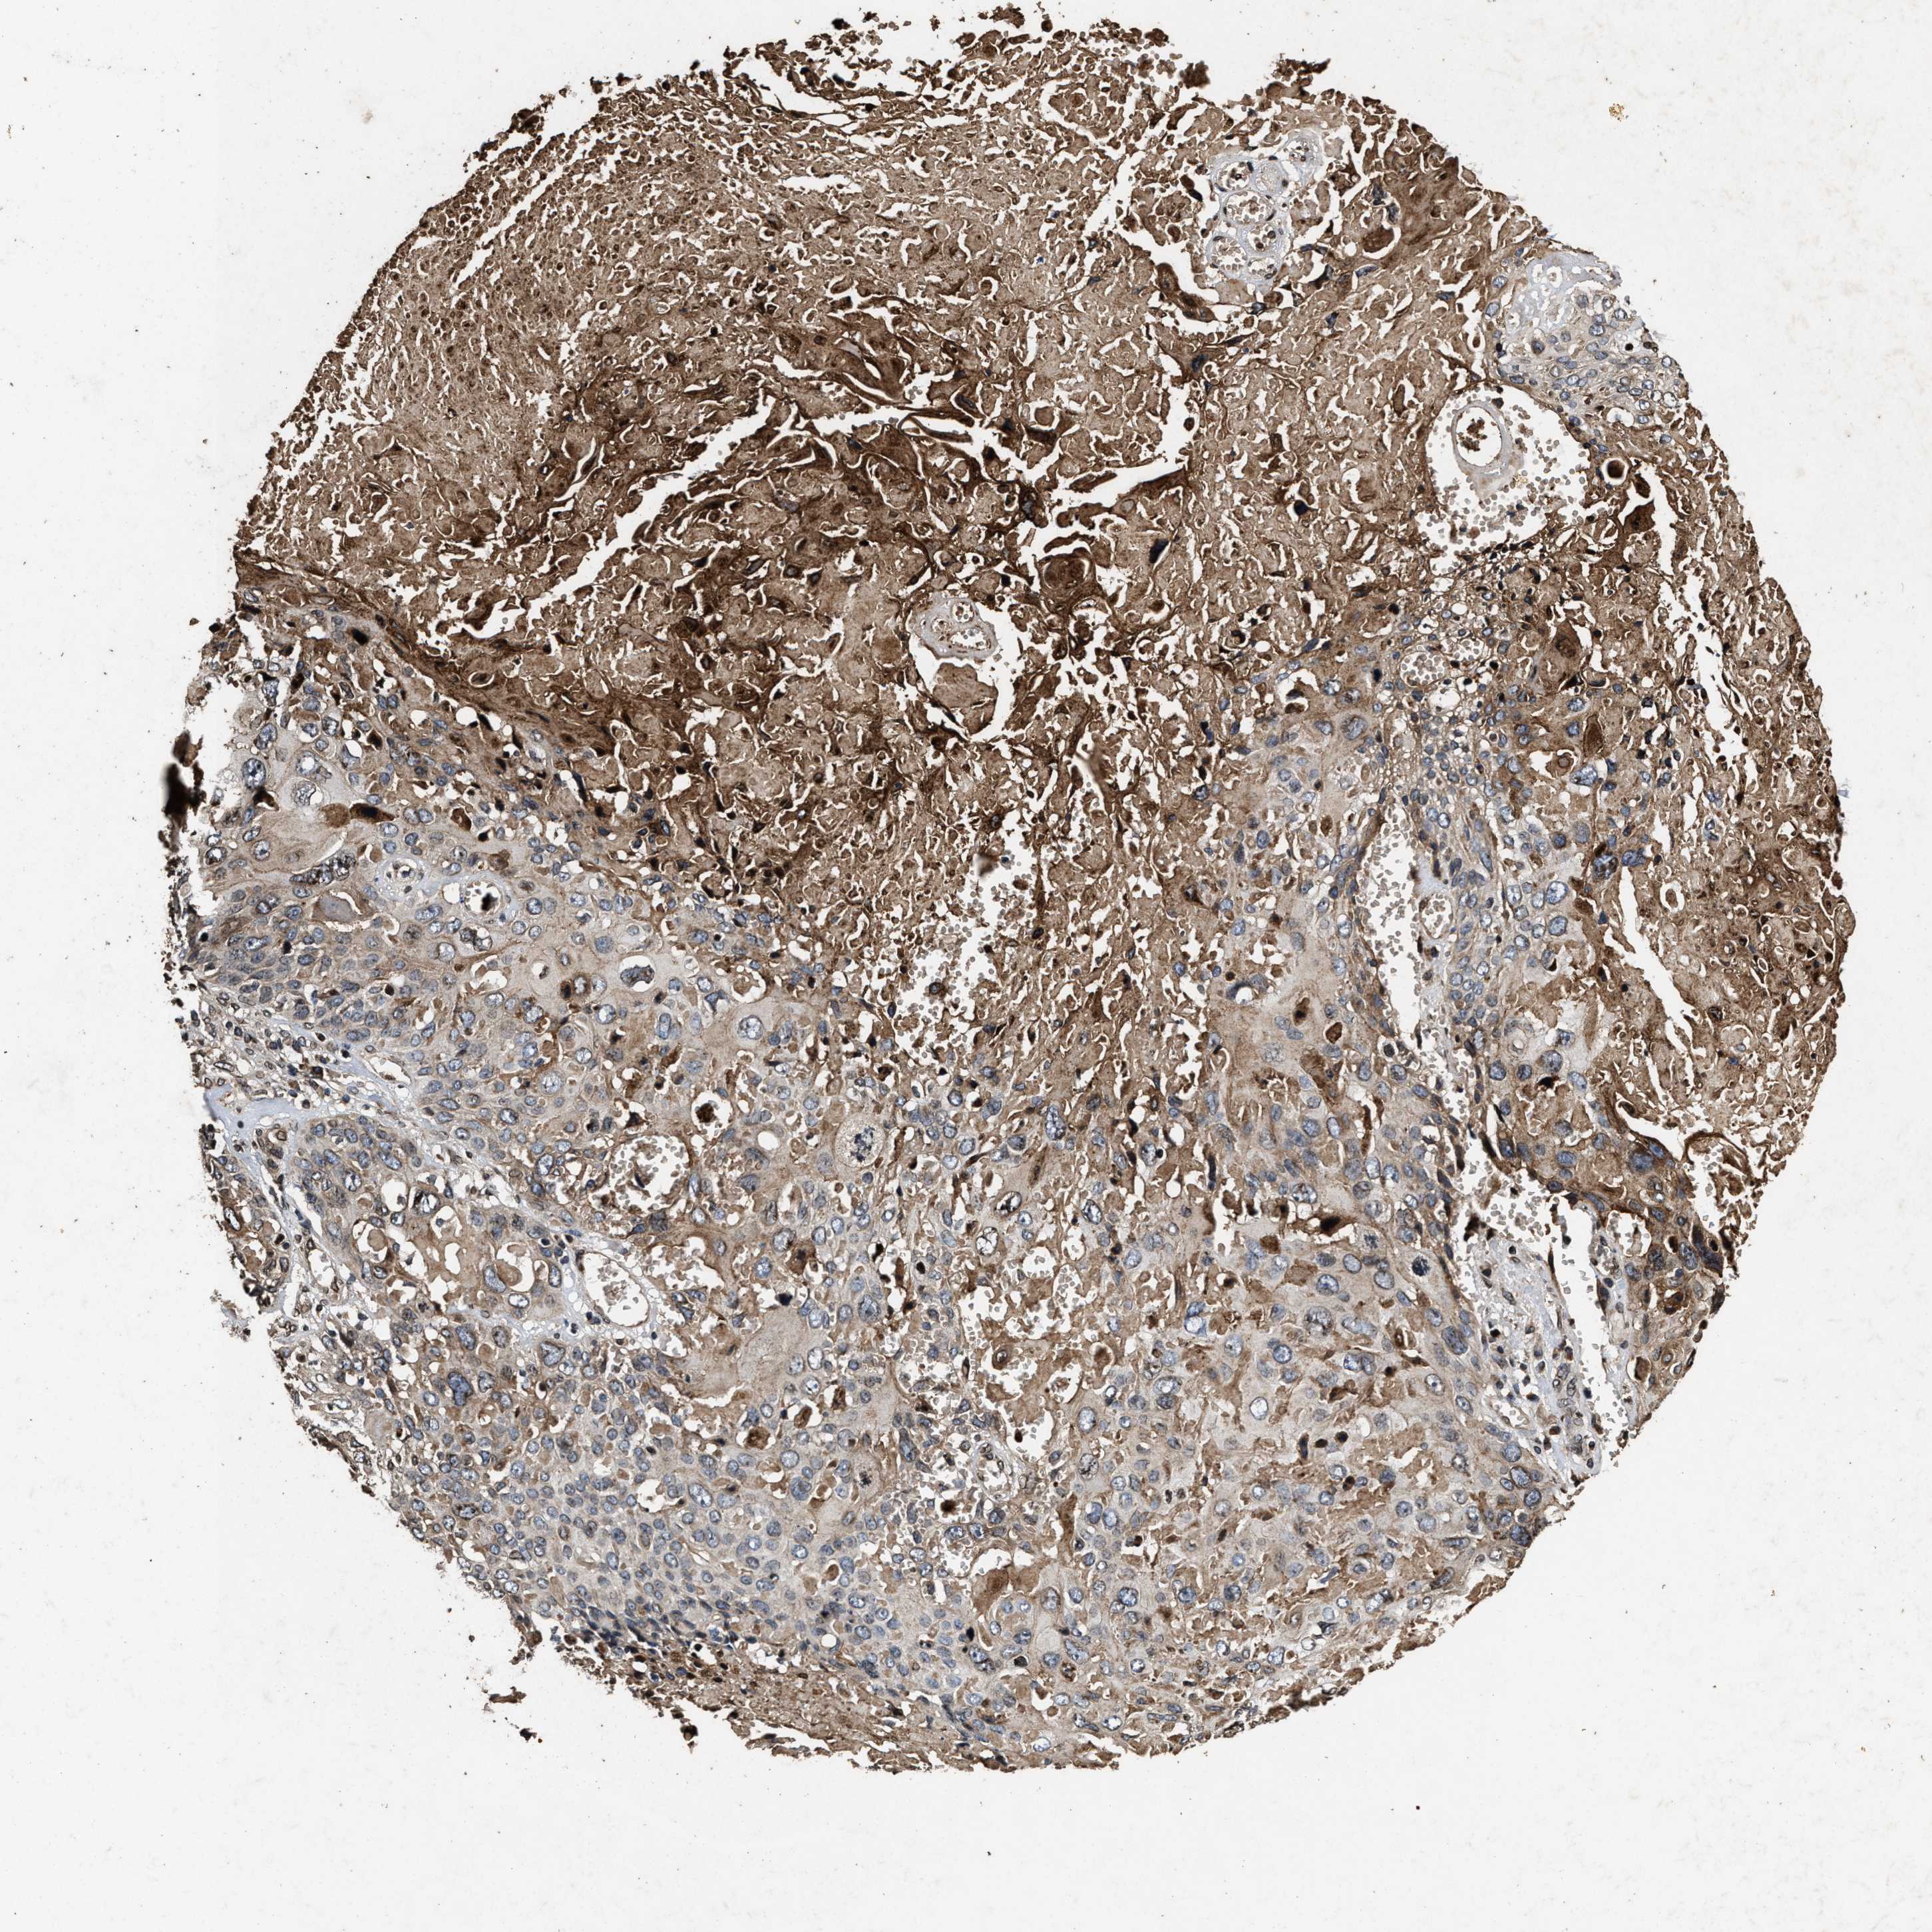

CERVICAL CANCER - Protein expressioni

A mouse-over function shows sample information and annotation data. Click on an image to view it in a full screen mode. Samples can be filtered based on level of antibody staining by selecting one or several of the following categories: high, medium, low and not detected. The assay and annotation is described here.

Note that samples used for immunohistochemistry by the Human Protein Atlas do not correspond to samples in the TCGA dataset.

Antibody stainingi

Antibody staining in the annotated cell types in the current human tissue is reported as not detected, low, medium, or high, based on conventional immunohistochemistry profiling in selected tissues. This score is based on the combination of the staining intensity and fraction of stained cells.

Each image is clickable and will lead to virtual microscopy that enables deeper exploration of all samples and also displays staining intensity scores, fraction scores and subcellular localization as well as patient and tissue information for each sample.

Antibody HPA018873

Antibody HPA021654

Staining

High

Medium

Low

Not detected

Intensity

Strong

Moderate

Weak

Negative

Quantity

>75%

75%-25%

<25%

None

Location

Nuclear

Cytoplasmic/membranous

Cytoplasmic/membranous,nuclear

Squamous cell carcinoma, NOS

Adenocarcinoma, NOS